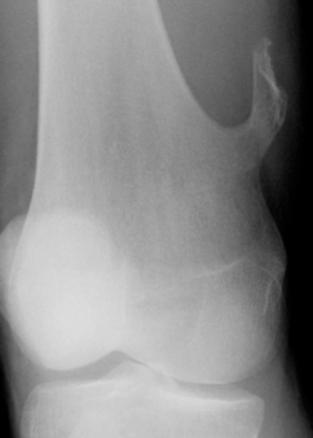

Exostose : saillie osseuse en continuité avec la corticale

Il s'agit d'une tumeur bénigne se formant au cours de la croissance mais persistant chez l'adulte. Elle peut être l'occasion de conflit avec les parties molles environnantes. Elles peuvent dégénérer sous forme maligne.